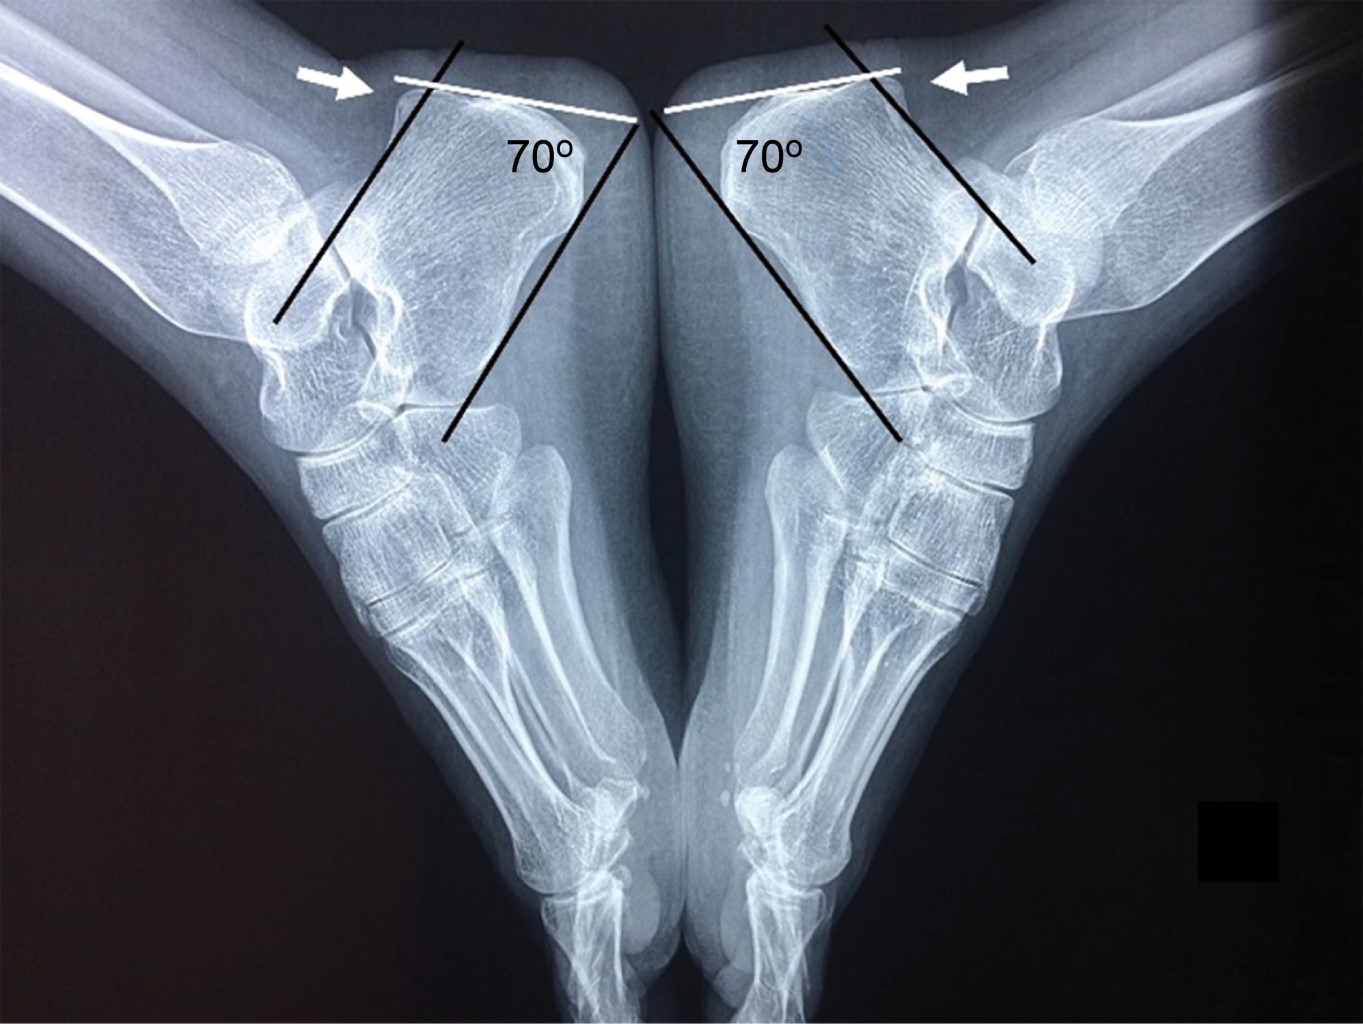

Figure 2